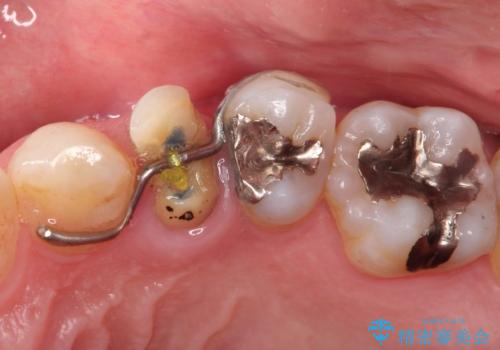

- 歯肉の下まで深く歯が折れたことを主訴に来院された患者様です。

かかりつけ医にて応急的に修復してますが根本的な治療を希望され、矯正的挺出を行ったのち、歯周外科を行い、歯冠修復をしております。